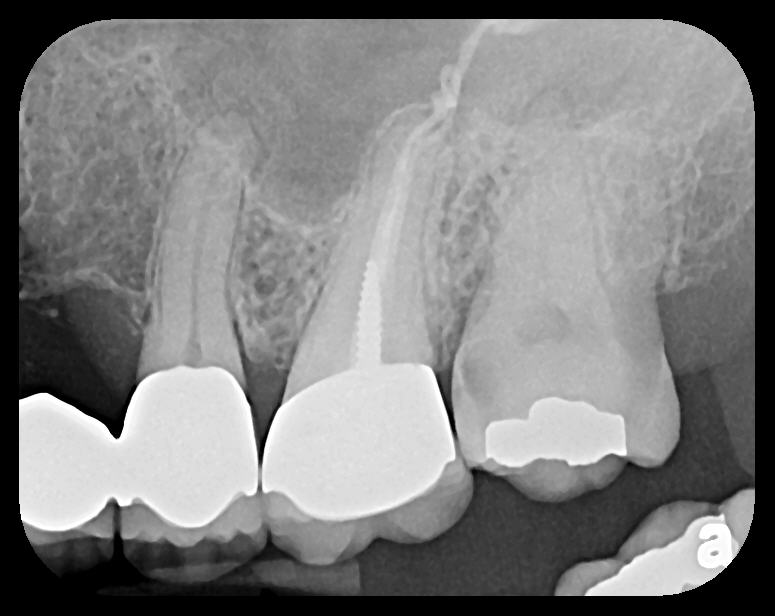

There are two specific types of DIDR sensor systems available to dentists in the marketplace: the hard-wired (HW) sensor and the photostimulable phosphor (PSP) sensor,1,2 also commonly known as phosphor "plates." A desirable feature common to both modalities is the ability to expose either bitewing (BW) or PA radiographic images. The BW radiograph (Figure 1) is usually considered more appropriate for caries detection, whereas the PA (Figure 2) is diagnostic for several different anatomic and pathologic issues.7

Fig 1. Left: Representative PSP BW radiograph with multiple restorative materials of varying radiographic densities. Tooth No. 31 demonstrates deep

caries on mesial aspect beneath the restorative. Radiolucency of carious lesion results from the low relative density of caries compared with healthy

tooth structure. Right: PSP BW radiograph optimized for view of multiple interproximal carious lesions.

Figure 1